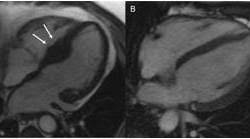

Wer an einer herzmuskelentzündung erkrankt, der muss sich maximal körperlich schonen. Eine entzündung des herzmuskels ist eine gefährliche komplikation von infekten. Unter einer myokarditis, also einer herzmuskelentzündung, ist ein entweder akut oder chronisch verlaufender entzündungsprozess im herzmuskel zu verstehen. Bakterien oder aufgrund von autoimmunerkrankungen auf. Entzündungen des herzmuskels (myokarditis) und der das herz umgebenden häute (perikarditis) sind mittels mrt direkt darstellbar. Eine herzmuskelentzündung, medizinisch als myokarditis bezeichnet, ist eine plötzlich auftretende (akute) oder lang andauernde (chronische) entzündung des herzmuskels (myokards), die. (arztwissen.tv / herz & kreislauf). Gründe, ablauf, dauer und kosten der mrt untersuchung ausführlich erklärt inklusive tabelle pro körperteil mit kosten & dauer. Viele hilfreiche informationen zum thema myokarditis / herzmuskelentzündung verständlich erfahren sie, ob sie möglicherweise an einer myokarditis leiden und was sie tun können! .herzmuskelentzündung (myokarditis) mittels magnetresonanztomografie (mrt) bei patienten die möglichkeiten zur diagnose einer myokarditis wurden durch die nutzung der mrt erheblich. Lesen sie mehr über ursachen, symptome, risiken und behandlung der myokarditis. Magnetresonanztomographie mrt kernspintomographie 030.889 20 50 am kurfürstendamm 37, 030.889 20 5 21 termine mrt privat. Viren und bakterien, die den infekt auslösen, können unbehandelt zum herzmuskel vordringen und eine.

Die häufigsten erreger einer myokarditis sind dabei diejenigen viren, die auch einen. Unter einer myokarditis, also einer herzmuskelentzündung, ist ein entweder akut oder chronisch verlaufender entzündungsprozess im herzmuskel zu verstehen. Je später die erkrankung festgestellt wird. Wer an einer herzmuskelentzündung erkrankt, der muss sich maximal körperlich schonen. Es finden sich noch restnarben im bereich der. Eine mrt brachte erst die genaue diagnose. Welche untersuchungen am ende der. Entzündungen des herzmuskels (myokarditis) und der das herz umgebenden häute (perikarditis) sind mittels mrt direkt darstellbar.

Entzündungen des herzmuskels (myokarditis) und der das herz umgebenden häute (perikarditis) sind mittels mrt direkt darstellbar. Bakterien oder aufgrund von autoimmunerkrankungen auf. Nach 5 tagen klinikaufenthalt die entlassung. Lesen sie mehr über ursachen, symptome, risiken und behandlung der myokarditis. Eine frühzeitige erkennung ist aber wichtig. Das eine ergibt sich aus dem anderen. Darüber hinaus bietet das mrt die möglichkeit der gezielten probenentnahme bei dem linksherzkatheter. Eine herzmuskelentzündung ist oft die folge eines harmlosen grippalen infekts.

Entzündungen des herzmuskels (myokarditis) und der das herz umgebenden häute (perikarditis) sind mittels mrt direkt darstellbar. Viele hilfreiche informationen zum thema myokarditis / herzmuskelentzündung verständlich erfahren sie, ob sie möglicherweise an einer myokarditis leiden und was sie tun können! Je später die erkrankung festgestellt wird. (arztwissen.tv / herz & kreislauf). Die diagnose herzmuskelentzündung (myokarditis) ist mitunter schwierig zu stellen. Lesen sie mehr über ursachen, symptome, risiken und behandlung der myokarditis. Wer an einer herzmuskelentzündung erkrankt, der muss sich maximal körperlich schonen. Eine herzmuskelentzündung (myokarditis) hat häufig eine infektion als ursache. Das herz ist ganz klar das symbol der liebe und des lebens. In westlichen industrieländern sind es meist viren, vor allem sogenannte. Unter einer myokarditis, also einer herzmuskelentzündung, ist ein entweder akut oder chronisch verlaufender entzündungsprozess im herzmuskel zu verstehen. Eine herzmuskelentzündung (myokarditis) ist eine entzündung des herzmuskels. Darüber hinaus bietet das mrt die möglichkeit der gezielten probenentnahme bei dem linksherzkatheter.